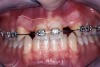

Before the day of surgery, the patient was seen by the orthodontist for the removal of the orthodontic brackets. The patient still was not pleased with the position of the two centrals, and it was determined that this would be addressed after implant placement (Figure 13A). The anatomical variations of the crestal tissue and lack of interdental papilla can be appreciated in the close-up views of the right and left sites (Figure 13B and 13C). There were no surprises on the day of surgery as all of the decisions were made during the planning phase, before the scalpel ever touched the patient. The occlusal view of the CT 3D model revealed the wider alveolar ridge on the right side and thinner crest on the left side (Figure 14A). This was confirmed when the full thickness mucoperiosteal flaps were elevated, and the underyling bone revealed (Figure 14B). The tooth-borne templates were designed to facilitate the drills and drilling sequence specific to the diameters of the predetermined implants (Figure 15A). Each template contained an embedded 5-mm long stainless steel tube, which was approximately 0.2-mm wider than each drill (just wide enough to allow for the drills to rotate freely). Once positioned over the natural teeth, the template was secure and offered precision accuracy in transferring the implant locations from the original software-designed plan, allowing the potential for internal and external irrigation (Figure 15B). The 3.7-mm diameter Tapered Screw-Vent implant drilling sequence requires three drills: pilot, intermediate, and final sizing. Thus, three separate templates were fabricated to a.commodate these sizes. The templates were removed easily and replaced with the next sequential size in less time than it takes to change the drill on the surgical handpiece. After the osteotomies had been.completed, the implants were delivered to the site (Figure 16A and Figure 16B). For this internal hex connection implant, the author r.commends that the flat of the antirotational hex be positioned to the facial for proper orientation of the restorative.components (Figure 17A). Preprepared margins were created from a milled titanium fixture mount transfer post, which was delivered to the implant as support for an immediate transitional restoration. The facial “dot” helped confirm the orientation of the abutment to the facially positioned flat side of the internal hex connection (Figure 17B). Before cementation of the transitional acrylic restorations, a closed-tray, fixture-level impression was made, and a soft-tissue model fabricated.

Figure 13a  Before implant surgery, the orthodontic brackets were removed, revealing (A) the position of the centrals, and (B, C) the anatomical variations of the crestal tissue and lack of interdental papilla.

Figure 13a

Figure 13b  Before implant surgery, the orthodontic brackets were removed, revealing (A) the position of the centrals, and (B, C) the anatomical variations of the crestal tissue and lack of interdental papilla.

Figure 13b

Figure 13c  Before implant surgery, the orthodontic brackets were removed, revealing (A) the position of the centrals, and (B, C) the anatomical variations of the crestal tissue and lack of interdental papilla.

Figure 13c